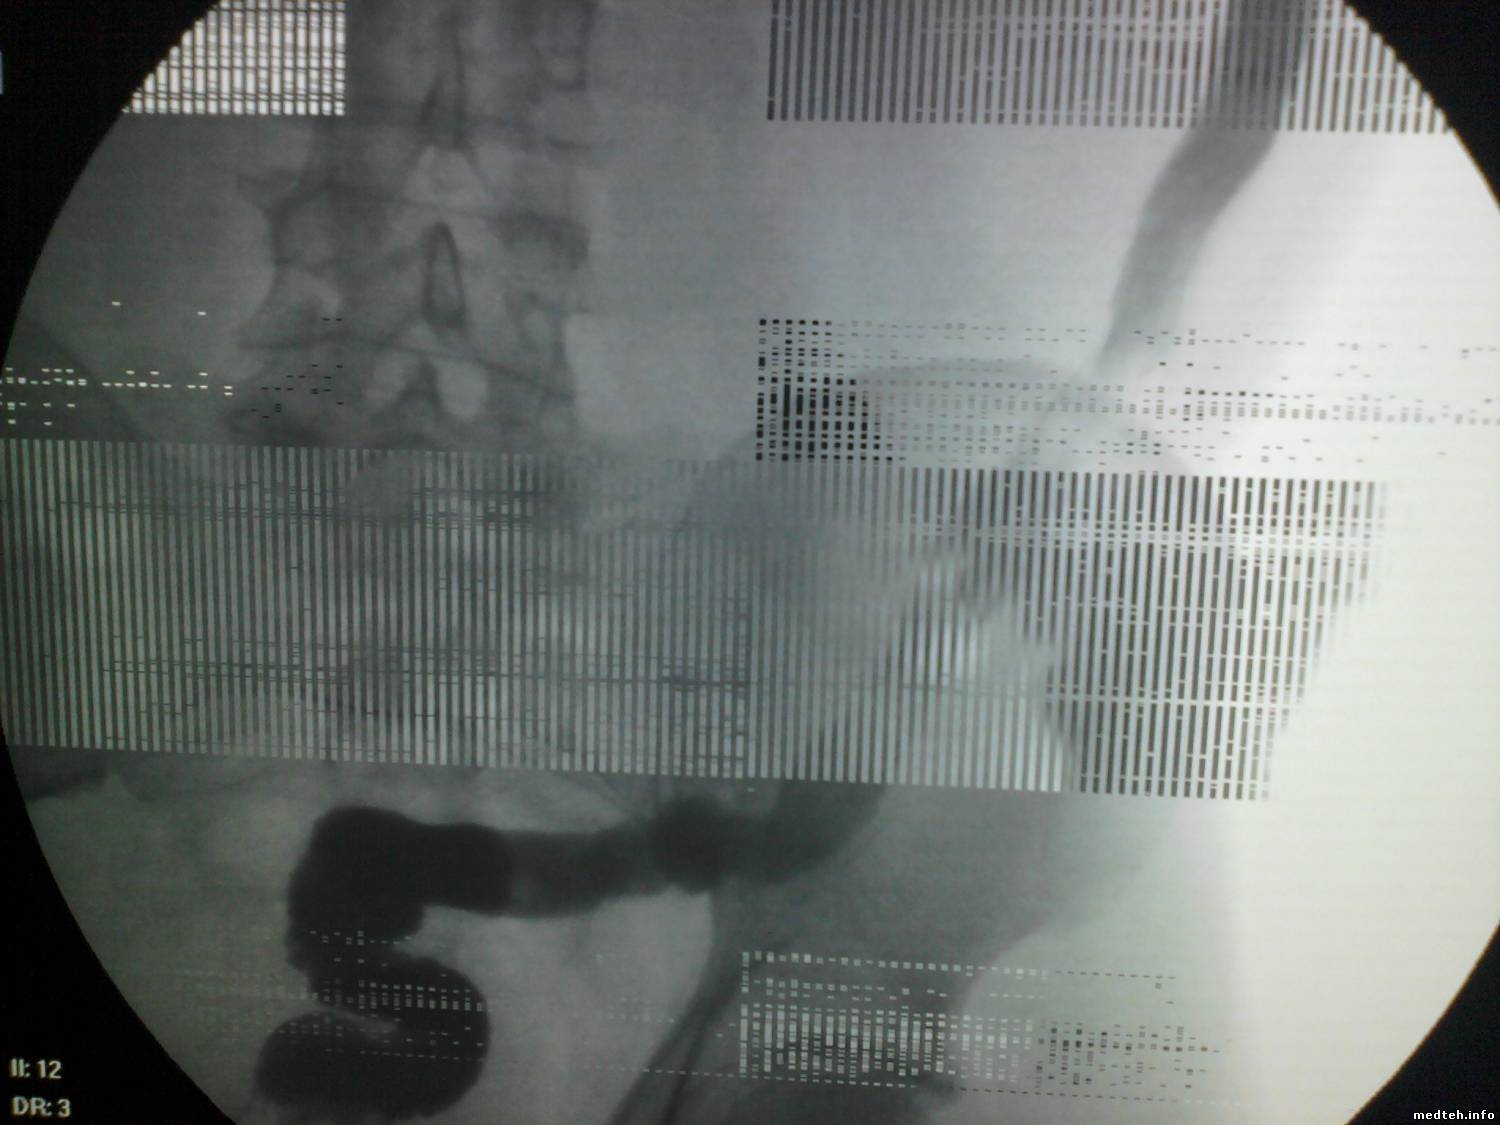

Во время скопического исследования (хотя замечено, что и в режиме покоя) на экране оператора появляются мерцающие полосы, мешающие работе. Грешили на внешние эл.помехи, заземлили все, что было можно - не помогло. Думаем теперь на УРИ.